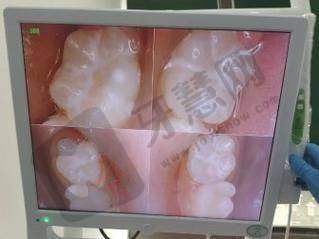

特色项目与技术优势:福州领先口腔门诊部有诸多特色项目。种植牙项目优势明显,温集英医生专注于种植牙领域多年,擅长处理高难度种植,推荐的韩国种植体(2680元,配全瓷牙冠)和瑞士ITI种植体(6000元,配全瓷牙冠),以高性价比吸引了众多患者。牙齿矫正项目也独具特色,骆珊珊医生不仅精通传统金属托槽矫正技术(23000元),还在隐形矫正方面有独到之处,主推正雅隐形矫正(16800元起),能满足不同患者的需求。此外,门诊部注重数字化口腔诊疗技术的引进和应用,引进了CBCT机、全景机等设备,为患者提供更精细、更舒适的口腔诊疗服务。